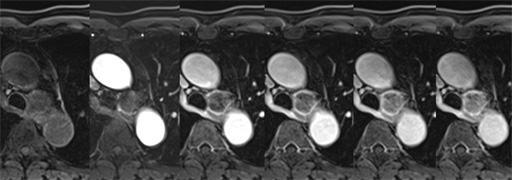

症例7 : 図11 MRI fat sat T1WI (dynamic study)